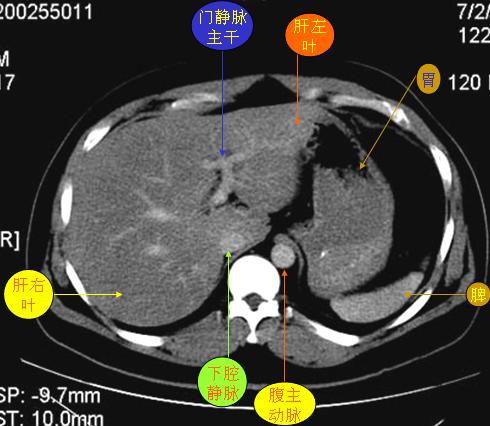

腹部ct解剖与基本病变